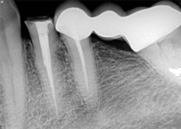

antes depois